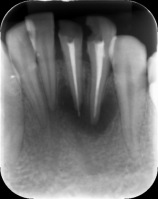

根管治疗前中后

但是稍微复杂性的牙病,必须拍片!拍牙片是为了让患者得到一种保障,提高医生诊断的准确性和成功率。如果不拍片的话,有可能导致治疗过程中无法正确把握位置等情况出现,从而影响治疗效果。